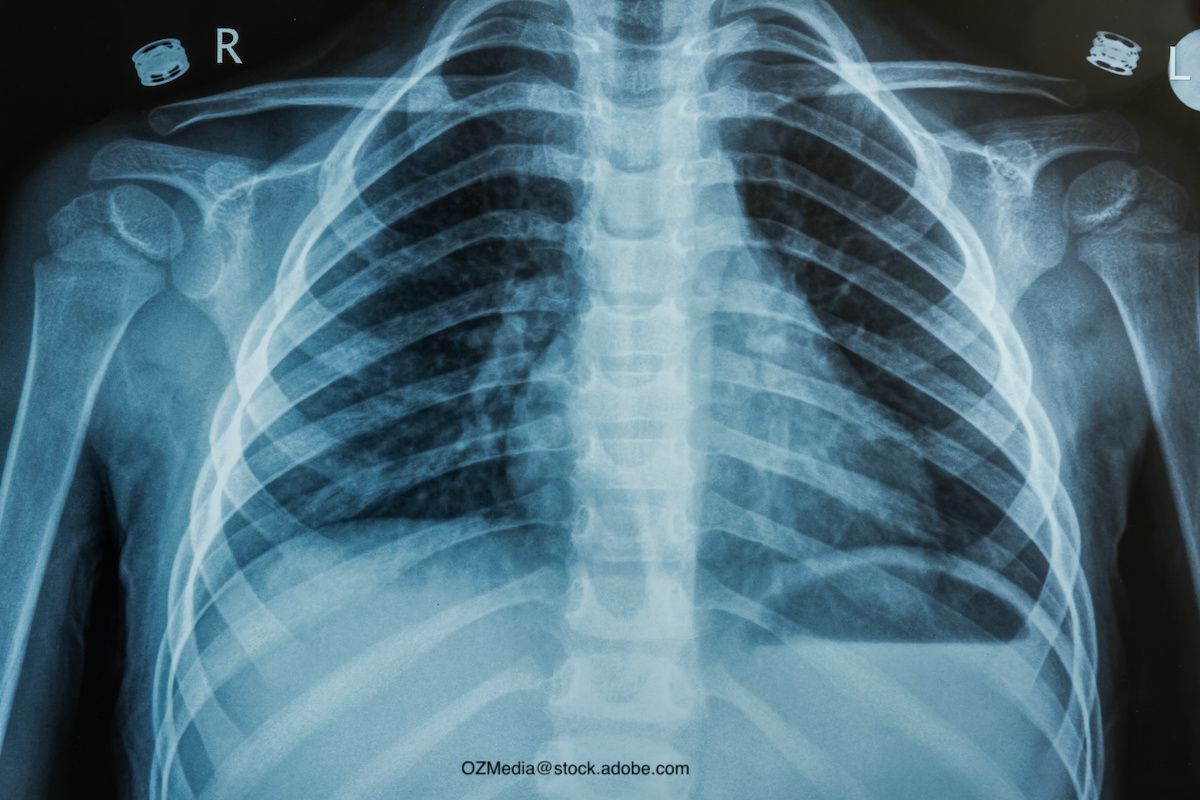

Many patients present with fever and cough, so how do you decide who has pneumonia and who should be treated with antibiotics? This is where the art of medicine plays a role. There are subtle findings that can help identify the child with pneumonia, such as grunting or an increased work of breathing; fever persisting beyond a few days; and sometimes it is just that the child looks sicker. You may hear decreased breath sounds or some crackles on the affected side. I have seen some patients come in with only a persistent fever and minimal other signs or symptoms. This is where the chest x-ray (CXR) could be helpful. However, even the CXR may not give us the answer, showing up as normal early in a pneumonia, and sometimes positive when it isn't pneumonia at all. Unilateral findings are typically more suggestive of a bacterial cause, with bilateral infiltrates being more commonly viral—but again, not always. It is not an easy task to differentiate bacterial from viral pneumonia and determine who needs antibiotics.

So what do we do? As pediatricians and diagnosticians, we have to put it all together: Is there a history of prior upper respiratory symptoms? Has fever been higher than expected and persistent? How does the child look? What are the vitals including oxygen saturations; and what are other findings on exam? Many times you can make the decision on a clinical basis, but a CXR can assist in the diagnosis. It is important to correctly diagnose CAP, yet there are no validated prognostic tools to help in the diagnosis. In the office setting, I do not find obtaining lab findings particularly helpful because the results are very nonspecific to viral vs bacterial pneumonia. If the white cell blood count (WBC) and/or C-reactive protein (CRP) are elevated, what does that tell you? A recent study of bio- markers and disease severity in children with CAP looked at the usefulness of WBC, CRP, and procalcitonin in predicting severity of CAP. Despite the usefulness in predicting severity of disease in adults, CRP and procalcitonin have not proved useful in children. The investigators did note that "CRP and procalcitonin may be useful in predicting the development of specific severe outcomes, such as complicated pneumonia and sepsis."2 Blood cultures are rarely helpful and should be reserved for the hospitalized patient.